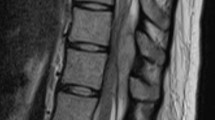

A 53-year-old man was admitted to our hospital with severe low back pain (LBP), lower extremity pain and numbness, and fever. Lumbar magnetic resonance imaging (MRI) revealed spondylodiscitis at L2–L3 and a small epidural abscess located ventrally in the spinal canal. Initially, the patient was treated conservatively with empirical antibiotics. However, the lower extremity symptoms worsened and the epidural abscess expanded cranially to the T12 level. Percutaneous pedicle screw fixation without decompression was performed thirty-three days after admission. Postoperatively, the LBP and lower extremity pain dramatically improved. A postoperative MRI performed one week post-operatively showed an unexpectedly rapid decrease in the size of the epidural abscess, although no decompression surgery was performed. Two months after surgery, the epidural abscess completely disappeared. At the final follow-up (five years postoperatively), no recurrence of epidural abscess was observed, and the patient had no symptoms or disturbance of activities of daily living.